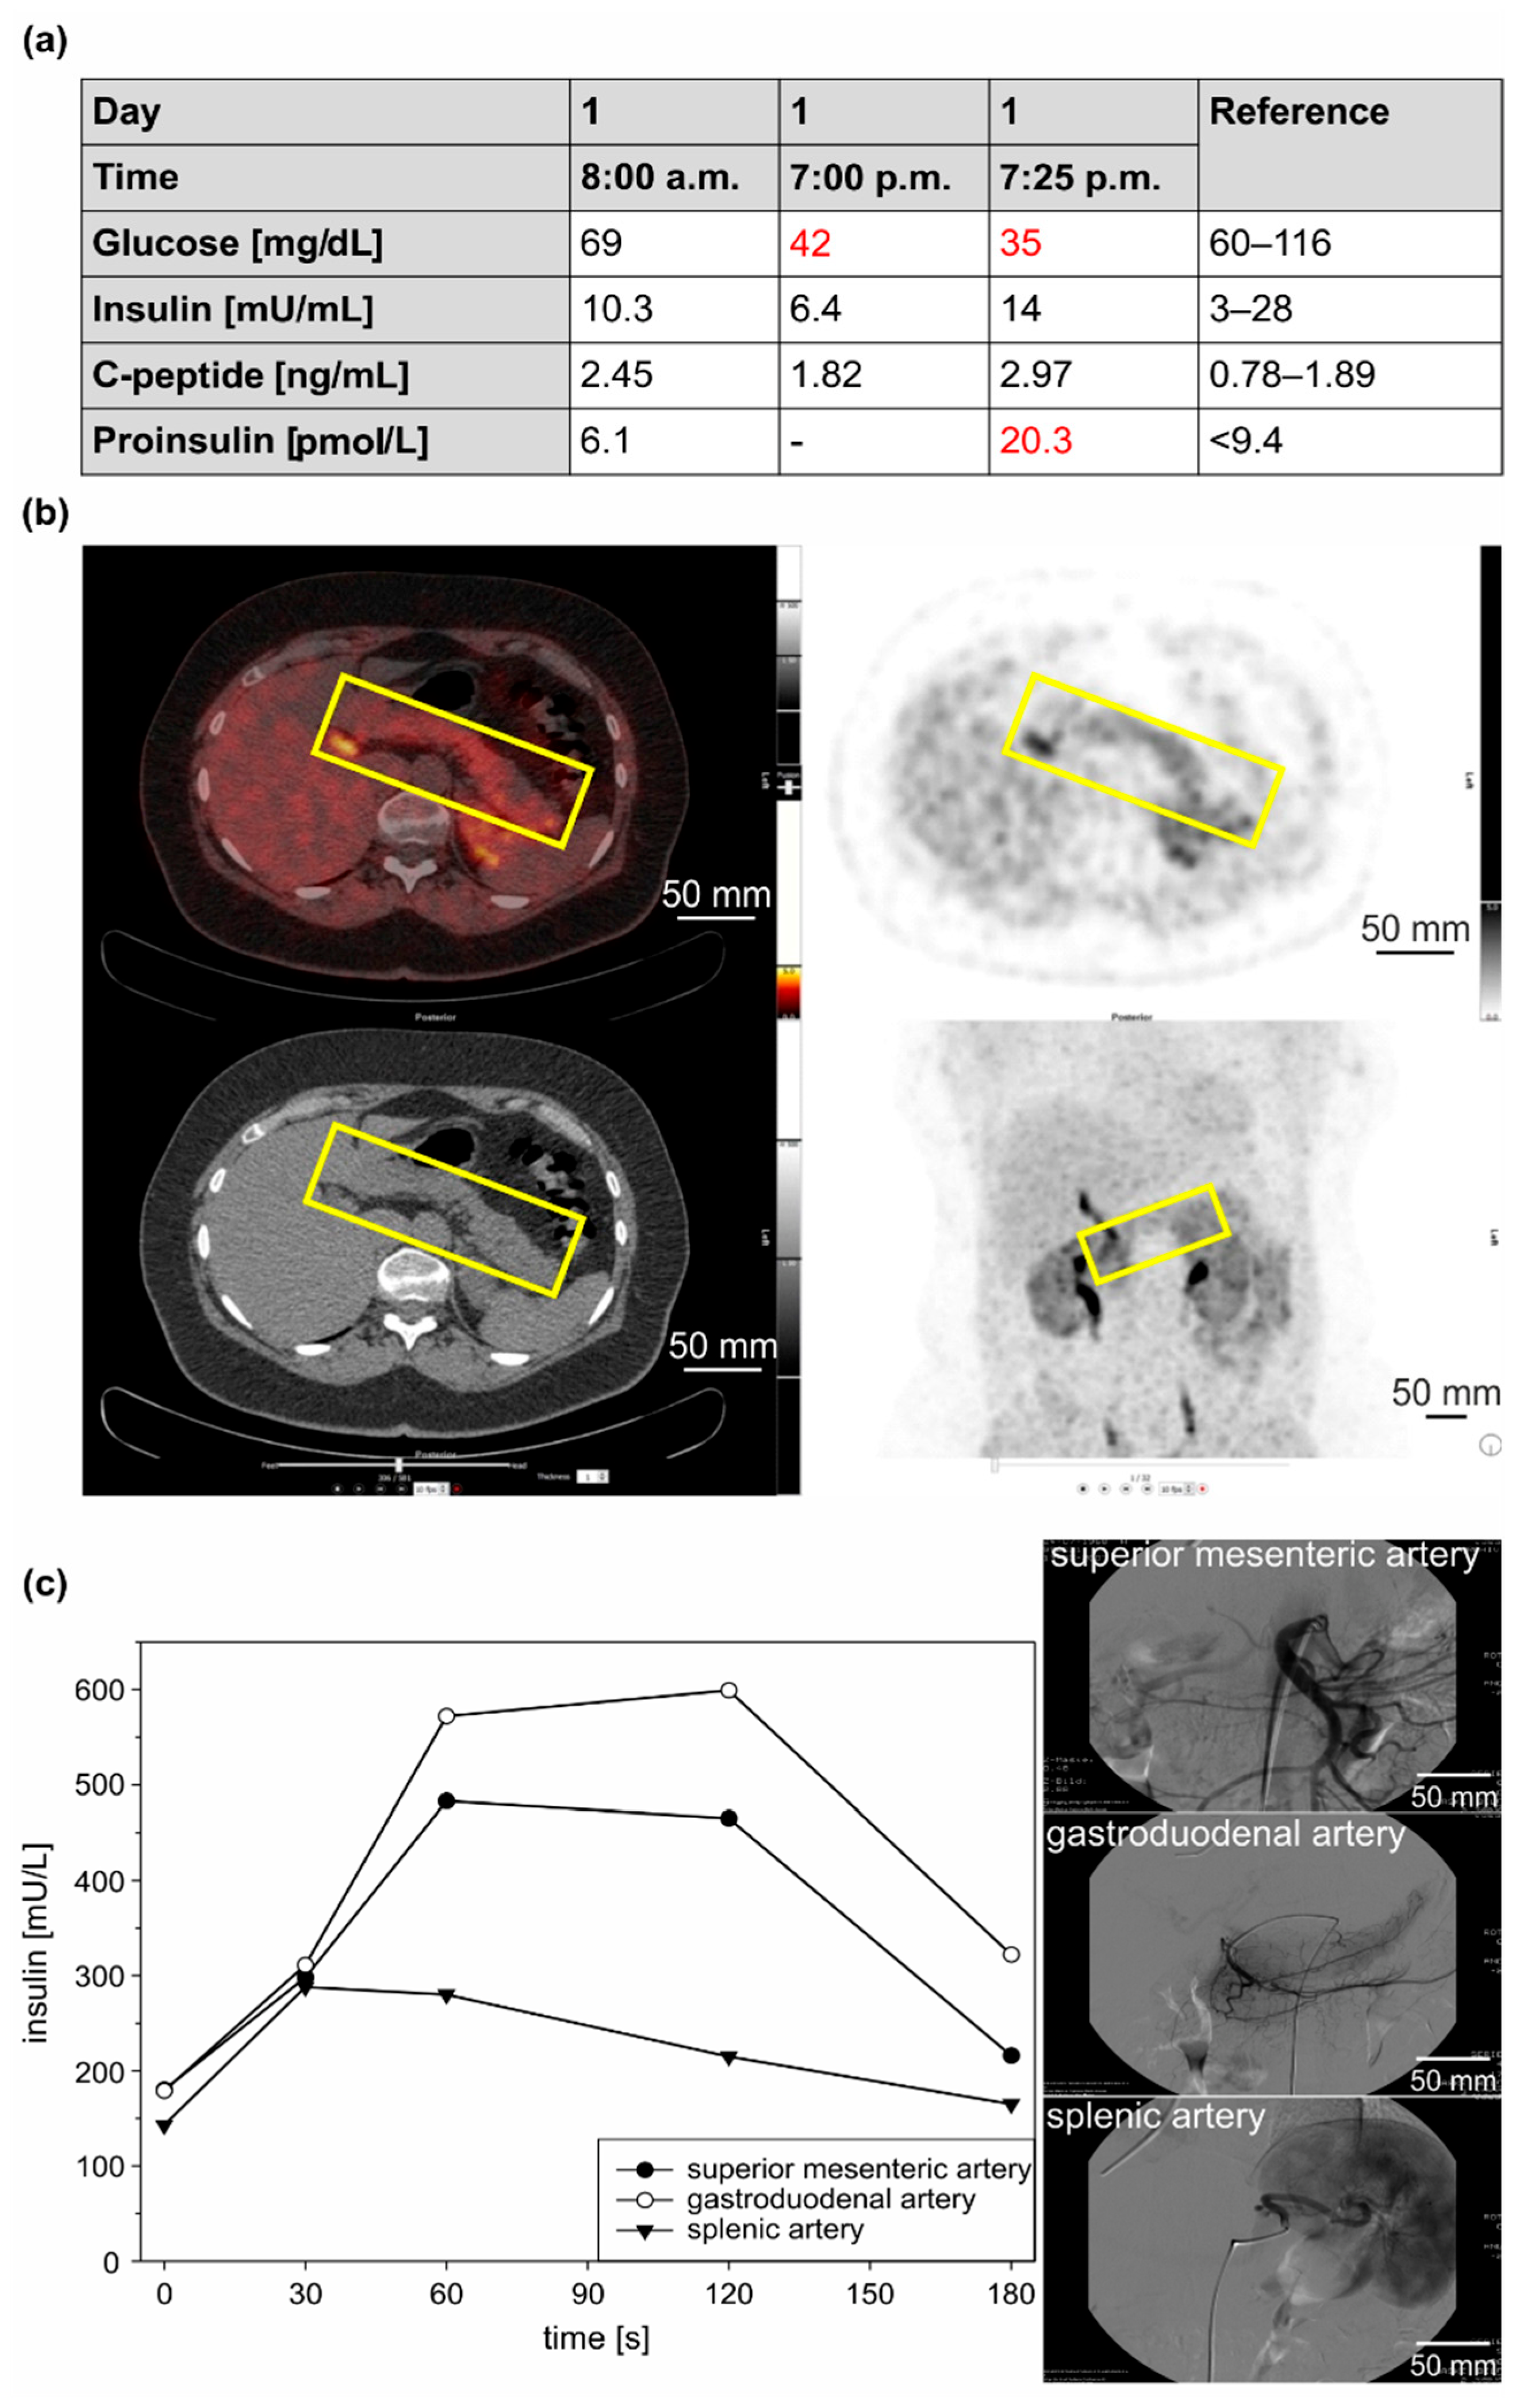

3.1.1. Clinical Case 1; Index Patient (Female, IV4, 48 Years Old at Time of Study)

3.1.2. Clinical Case 2; Sister of Clinical Case 1 (IV3, 57 Years Old at Time of Study)